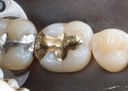

Matt Dodson #30 prep